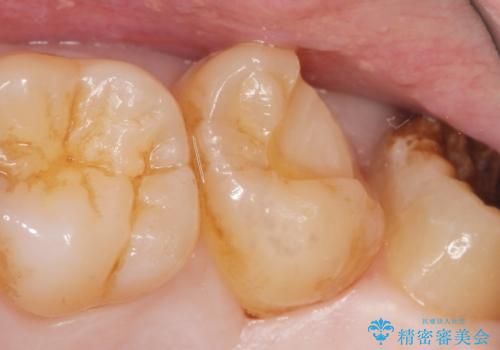

- 奥歯に食べ物がはさまることを主訴に来院された患者様です。

精査したところ、神経近くに及ぶ大きなう蝕を認めました。

神経をとらずに済むよう丁寧にう蝕を除去したのち、セラミックインレーで修復しました。